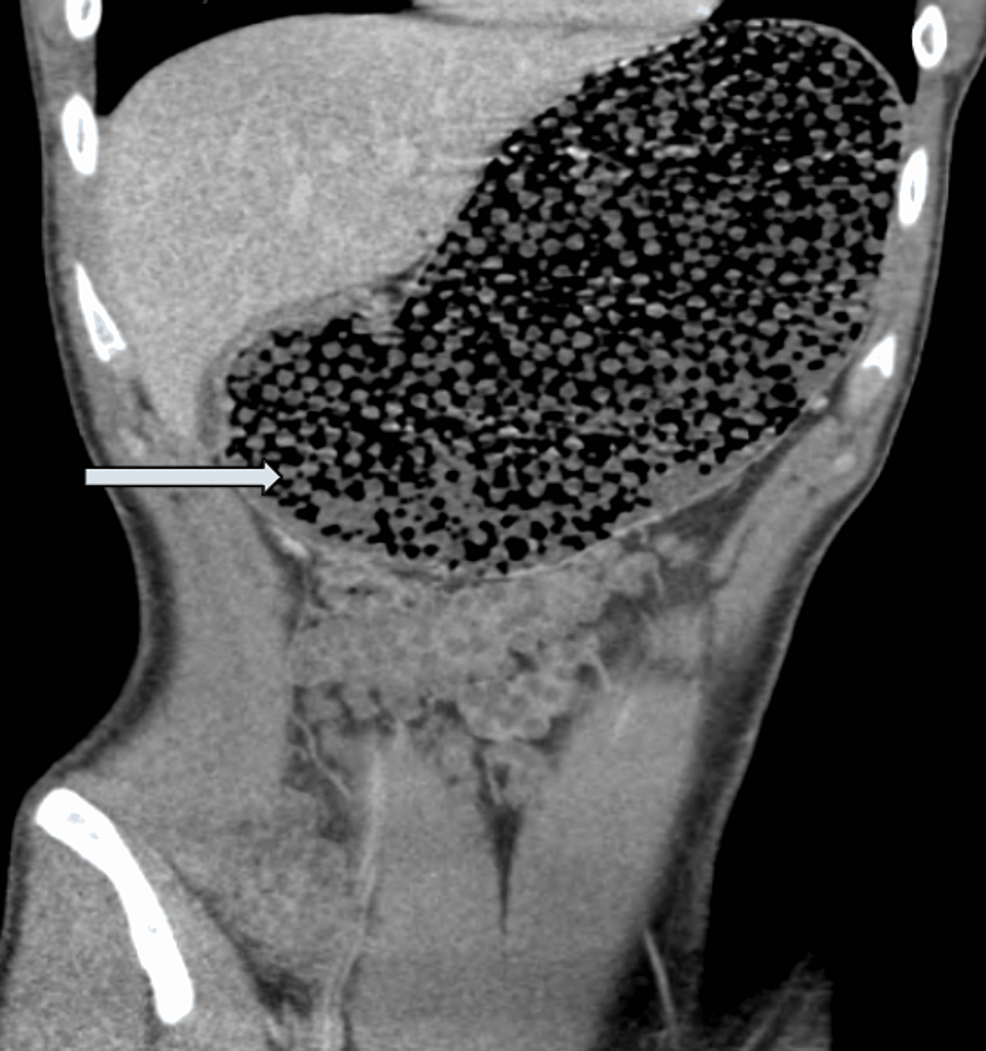

String of Beads SignSmall Bowel Obstruction Sumer's Radiology Blog Water Beads Xray If there is obviously a water bead in the intestine, attempts will be made to remove it via either endoscopy or surgery. However, they may be spotted using ultrasound, but as with any ultrasound, some of the beads may be missed. Ingested water beads can be readily detected on pocus given the physical and. Water beads, often sold as toys,. Water Beads Xray.

The Gastric Obstruction Due to Orbeez Beads Ingestion A Case Report Water Beads Xray Ingested water beads can be readily detected on pocus given the physical and. If there is obviously a water bead in the intestine, attempts will be made to remove it via either endoscopy or surgery. The label says 'nontoxic.' but are they? What is new in the. However, they may be spotted using ultrasound, but as with any ultrasound, some. Water Beads Xray.